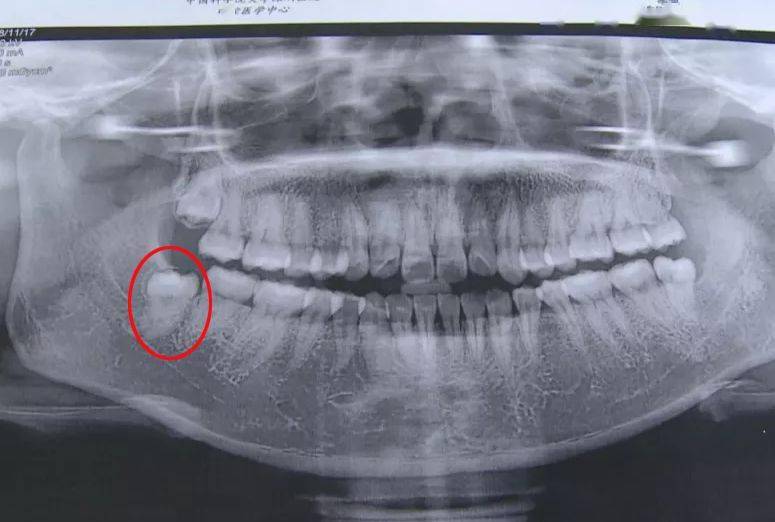

记者通过采访医生得知,她长的这颗智齿比一般的智齿拔起来困难得多,因为她的这颗智牙需要做很多项检查和护理,也多了很多步骤,所以这个收费也是按照标准收取的。

记者通过采访医生得知,她长的这颗智齿比一般的智齿拔起来困难得多,因为她的这颗智牙需要做很多项检查和护理,也多了很多步骤,所以这个收费也是按照标准收取的

1.2 恰当检查 包括高质量的X线片,它不仅能提供牙齿的清晰图像,牙根的轮廓和解剖以及牙周骨质情况,还能提供牙齿与邻牙和其他结构之间的关系,其中尤其是下颌骨下缘、下颌骨升支以及下牙槽神经束之间的关系